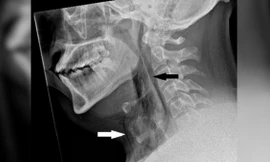

TPO - Thế giới vừa ghi nhận trường hợp đầu tiên được biết khi một người đàn ông đã rách một lỗ nhỏ trên khí quản sau khi cố gắng nhịn hắt hơi. Nếu bạn đã từng cố nhịn hắt hơi, báo cáo trường hợp y tế mới này có thể khiến bạn phải suy nghĩ kỹ.